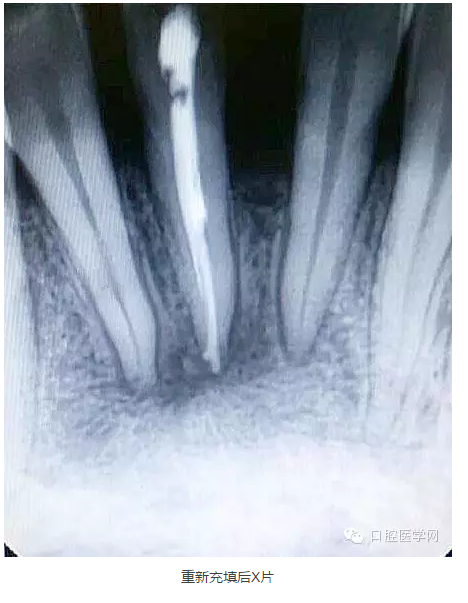

9.觀察一個(gè)月后打開暫封物拔出牙膠尖,檢查根管內(nèi)是否有滲出液,如果根管基本干燥,可再次沖洗消毒后根充,仍有滲出液者應(yīng)查明情況繼續(xù)治療。

下面是一例 今年年初治療的下前牙根尖囊腫病例,患者因故未能按時(shí)復(fù)診,最近才來。